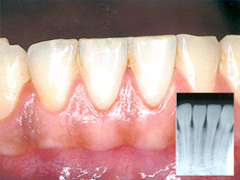

中等度歯周病

中度歯周病

状態 : プラーク(歯の汚れ)が固まることによって、歯石となります。

症状 : 歯ぐきが赤くはれ上がり、ぶよぶよしてきます。骨が溶けだす場合もあります。歯ぐきから血やうみが出て口臭も強くなります。

治療法 : 外科手術(歯ぐきを切開して歯石やプラークをとる)や歯周再生療法(歯槽骨などの組織を再生する)が必要になります。